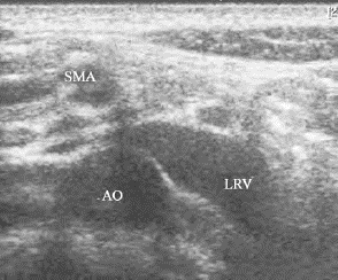

1.36.4四、腹腔大血管